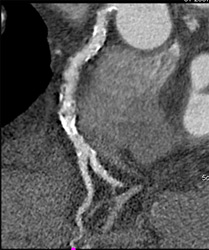

Diagnosis

Diseased RCA